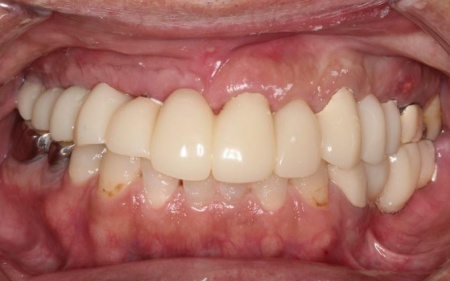

50代男性 バランスが崩れた噛み合わせをインプラント治療と被せ物治療で改善した症例

患者様は「見た目の自然さと、しっかり噛めることを重視したい」とのことで、欠損部の治療にはインプラントを選択され、合わなくなった被せ物や詰め物などの作り替えにも同意いただきました。

インプラントが骨にしっかりとなじんだことを確認したら、白くて強度の高い人工歯「ジルコニアクラウン」を装着しました。

最後に、見た目や噛み合わせに問題がないかを確認し、治療を終了しています。